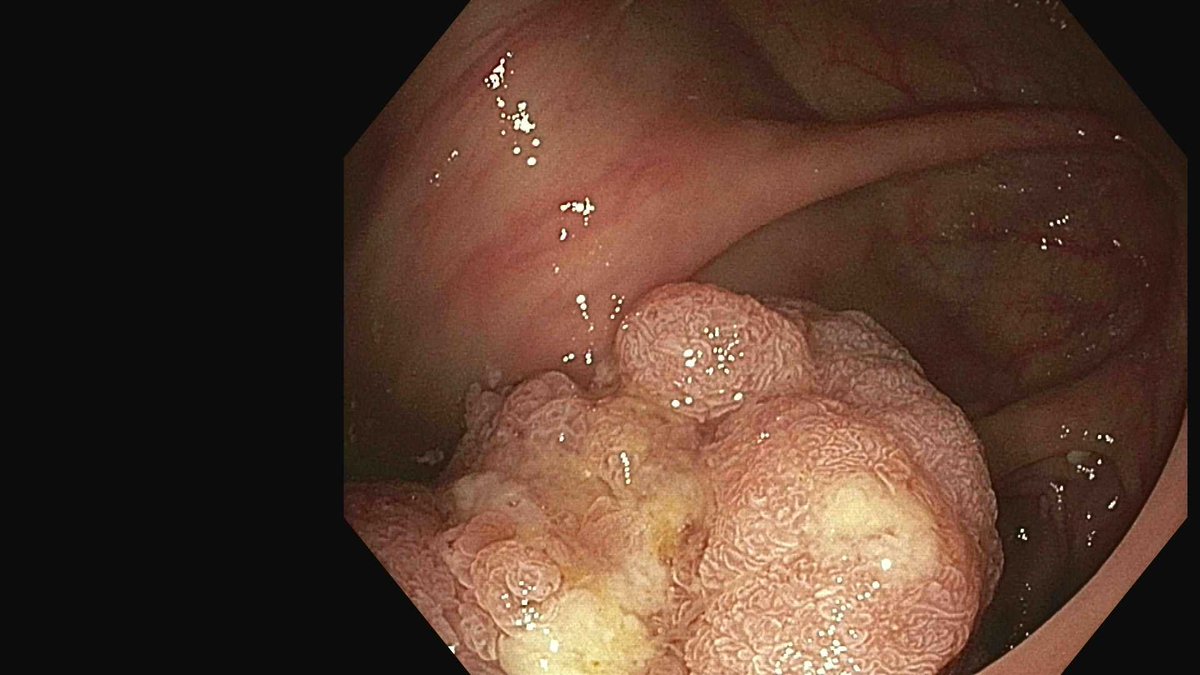

Great example of controlled removal of tissue persistence with EndoRotor in the cecum. Precise vacuum that can be increased or decreased based on tissue response is a key contributor to our low adverse event rate. #endoscopy #innovationinhealthcare #EndoRotor

English